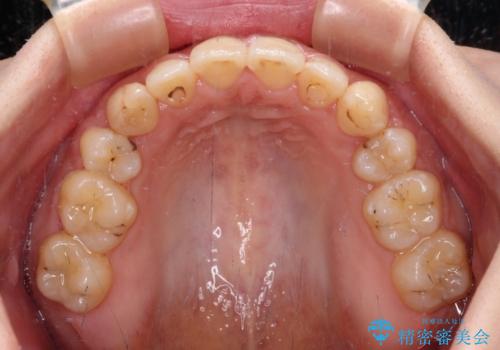

八重歯を抜歯矯正でスッキリと メタルブラケットでの矯正治療

- 矯正装置

- メタルブラケット

- 八重歯と上下前歯のでこぼこを気にして来院された患者様です。

上下前歯部叢生のスペース獲得のため、上下顎左右小臼歯各1歯(計4本)と全ての親知らずを抜歯して、矯正治療を行うこととしました。